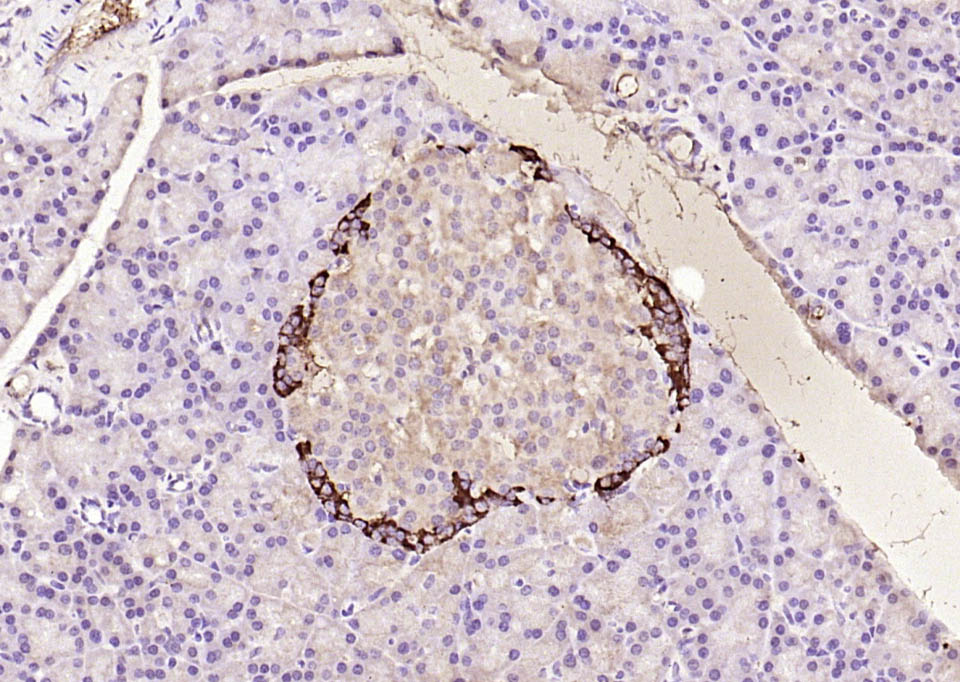

| 英文名称 | GLP-1 (7-36) Rabbit pAb |

| 中文名称 | 胰高血糖素样肽-1抗体 |

| 英文别名 | GCG; GLP 1; glucagon; Glucagon like peptide 1; GRPP; GLP-1(7-36); GLP-1(7-37); Oxyntomodulin; OXM; OXY; GLUC_HUMAN. |

| 产品应用 | IHC-P=1:100-500, IHC-F=1:100-500, IF=1:100-500 Not yet tested in other applications. |

| 交叉反应 | Human, Mouse, Rat (Pig, Cow, Sheep) |

| 组织特异性 | Glucagon is secreted in the A cells of the islets of Langerhans. GLP-1, GLP-2, oxyntomodulin and glicentin are secreted from enteroendocrine cells throughout the gastrointestinal tract. GLP1 and GLP2 are also secreted in selected neurons in the brain. |

| {IHC-P} | {1:100-500} |

| {IHC-F} | {1:100-500} |

| {IF} | {1:100-500} |